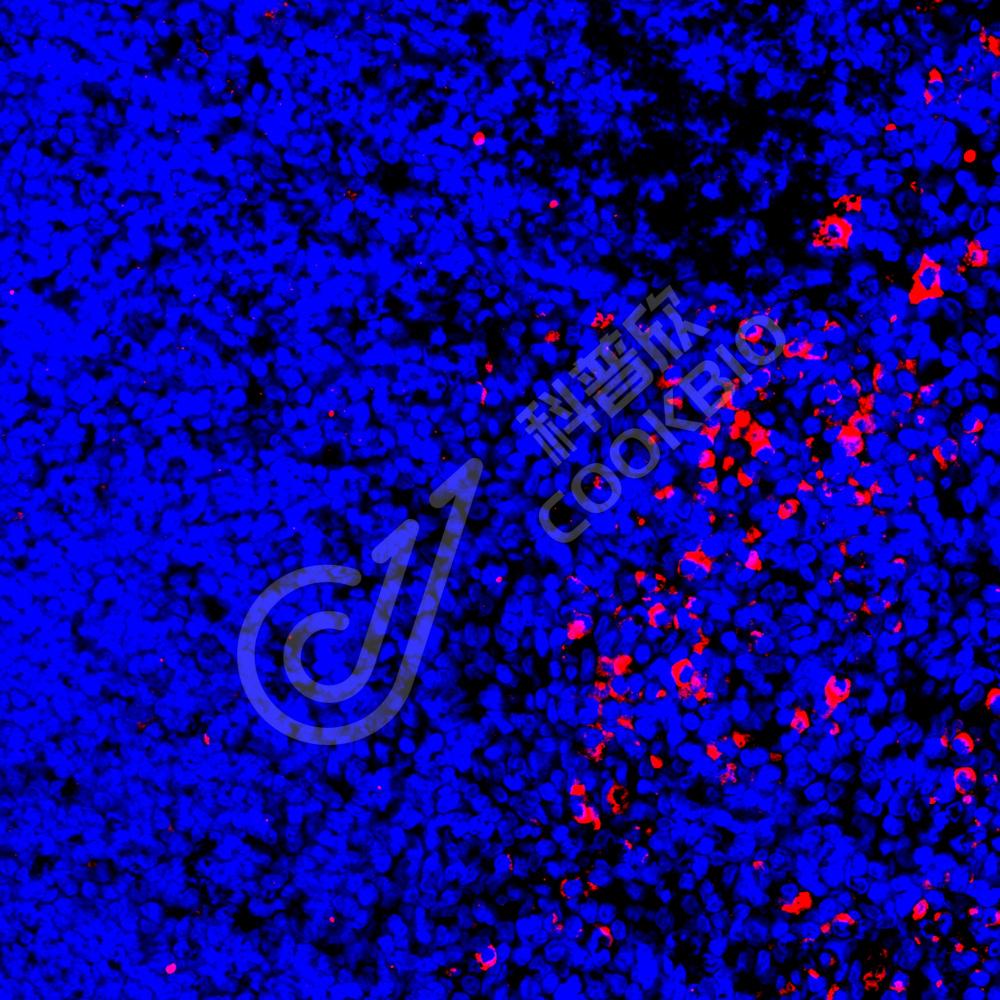

IF检测IL-9蛋白(货号 K135052)(红色).

样品: 大鼠LPS诱导的脓毒症模型肺, 4%多聚甲醛 (货号KSG1101) 固定12-24小时.

抗原修复: Tris-EDTA抗原修复液(pH 9.0) (KSG1203), 98℃, 20分钟.

封闭: 3% BSA(货号KSGC305010)的PBS溶液, 室温孵育30分钟.

—抗: 1: 1900稀释, 4℃ 孵育过夜.

二抗: Cy3标记山羊抗兔IgG (H+L) (货号KB63909), 1: 300稀释, 室温孵育1小时.